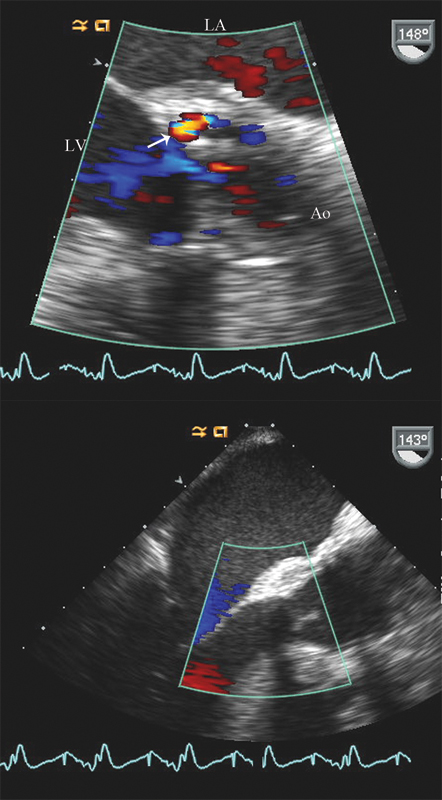

فحوصات تشخيصية لبعض امراض القلب والشرايين التاجية